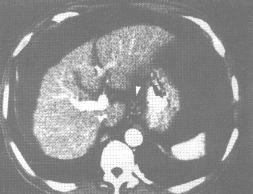

7.心血管病變:復發性多軟骨炎亦可累及心血管系統,發生率為30%,包括主動脈瘤,主動脈瓣大血管栓塞、小血管或大血管炎症和心臟瓣膜損害,心包炎及心肌缺血等。並可引起死亡。此外,在心血管併發症中還有兩個致命的災禍:一個是由完全性傳導阻滯和急性主動脈瓣閉鎖不全引致的心血管虛脫;另一個是主動脈瓣破裂。大血管受累可引致血管動脈瘤(主動脈、鎖骨下動脈),或由於血管炎或凝血病變而致的血栓形成。小血管受累時則表現為白細胞碎裂性血管炎。一般男性病人主動脈受累常見,表現為主動脈環及降主動脈進行性擴張,有些病例可出現升主動脈瘤胸、腹、主動脈及鎖骨下動脈發生動脈瘤。

其他檢查,如肺功能實驗(尤其是伴有咳嗽和呼吸困難時)、超聲心動圖、心導管、血管造影等在出現心血管症狀和體徵時均應考慮。

心臟超聲檢查可發現升主動脈瘤或降主動脈瘤心包炎、心肌收縮受損、二尖瓣或三尖瓣反流、心房血栓等。心電圖可出現Ⅰ度或完全房室傳導阻滯。